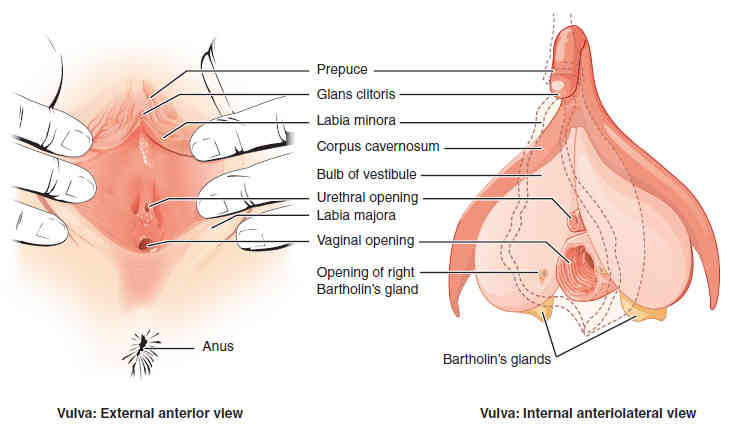

This page is under construction. For now, it is just a resource of the images found in the OpenStax Anatomy and Physiology Handbook. It wil slowly change into a revision tool. Each slide has a number. Use this to refer to the slide. When completed, it will have an unlabelled section, with labelled slides in parallel. On the unlabelled slides, write your answer and use the labelled slide to assess yourself. Keep track by also noting the number on each slide. Improvement at each attempt is important, more so than full marks on a first attempt.